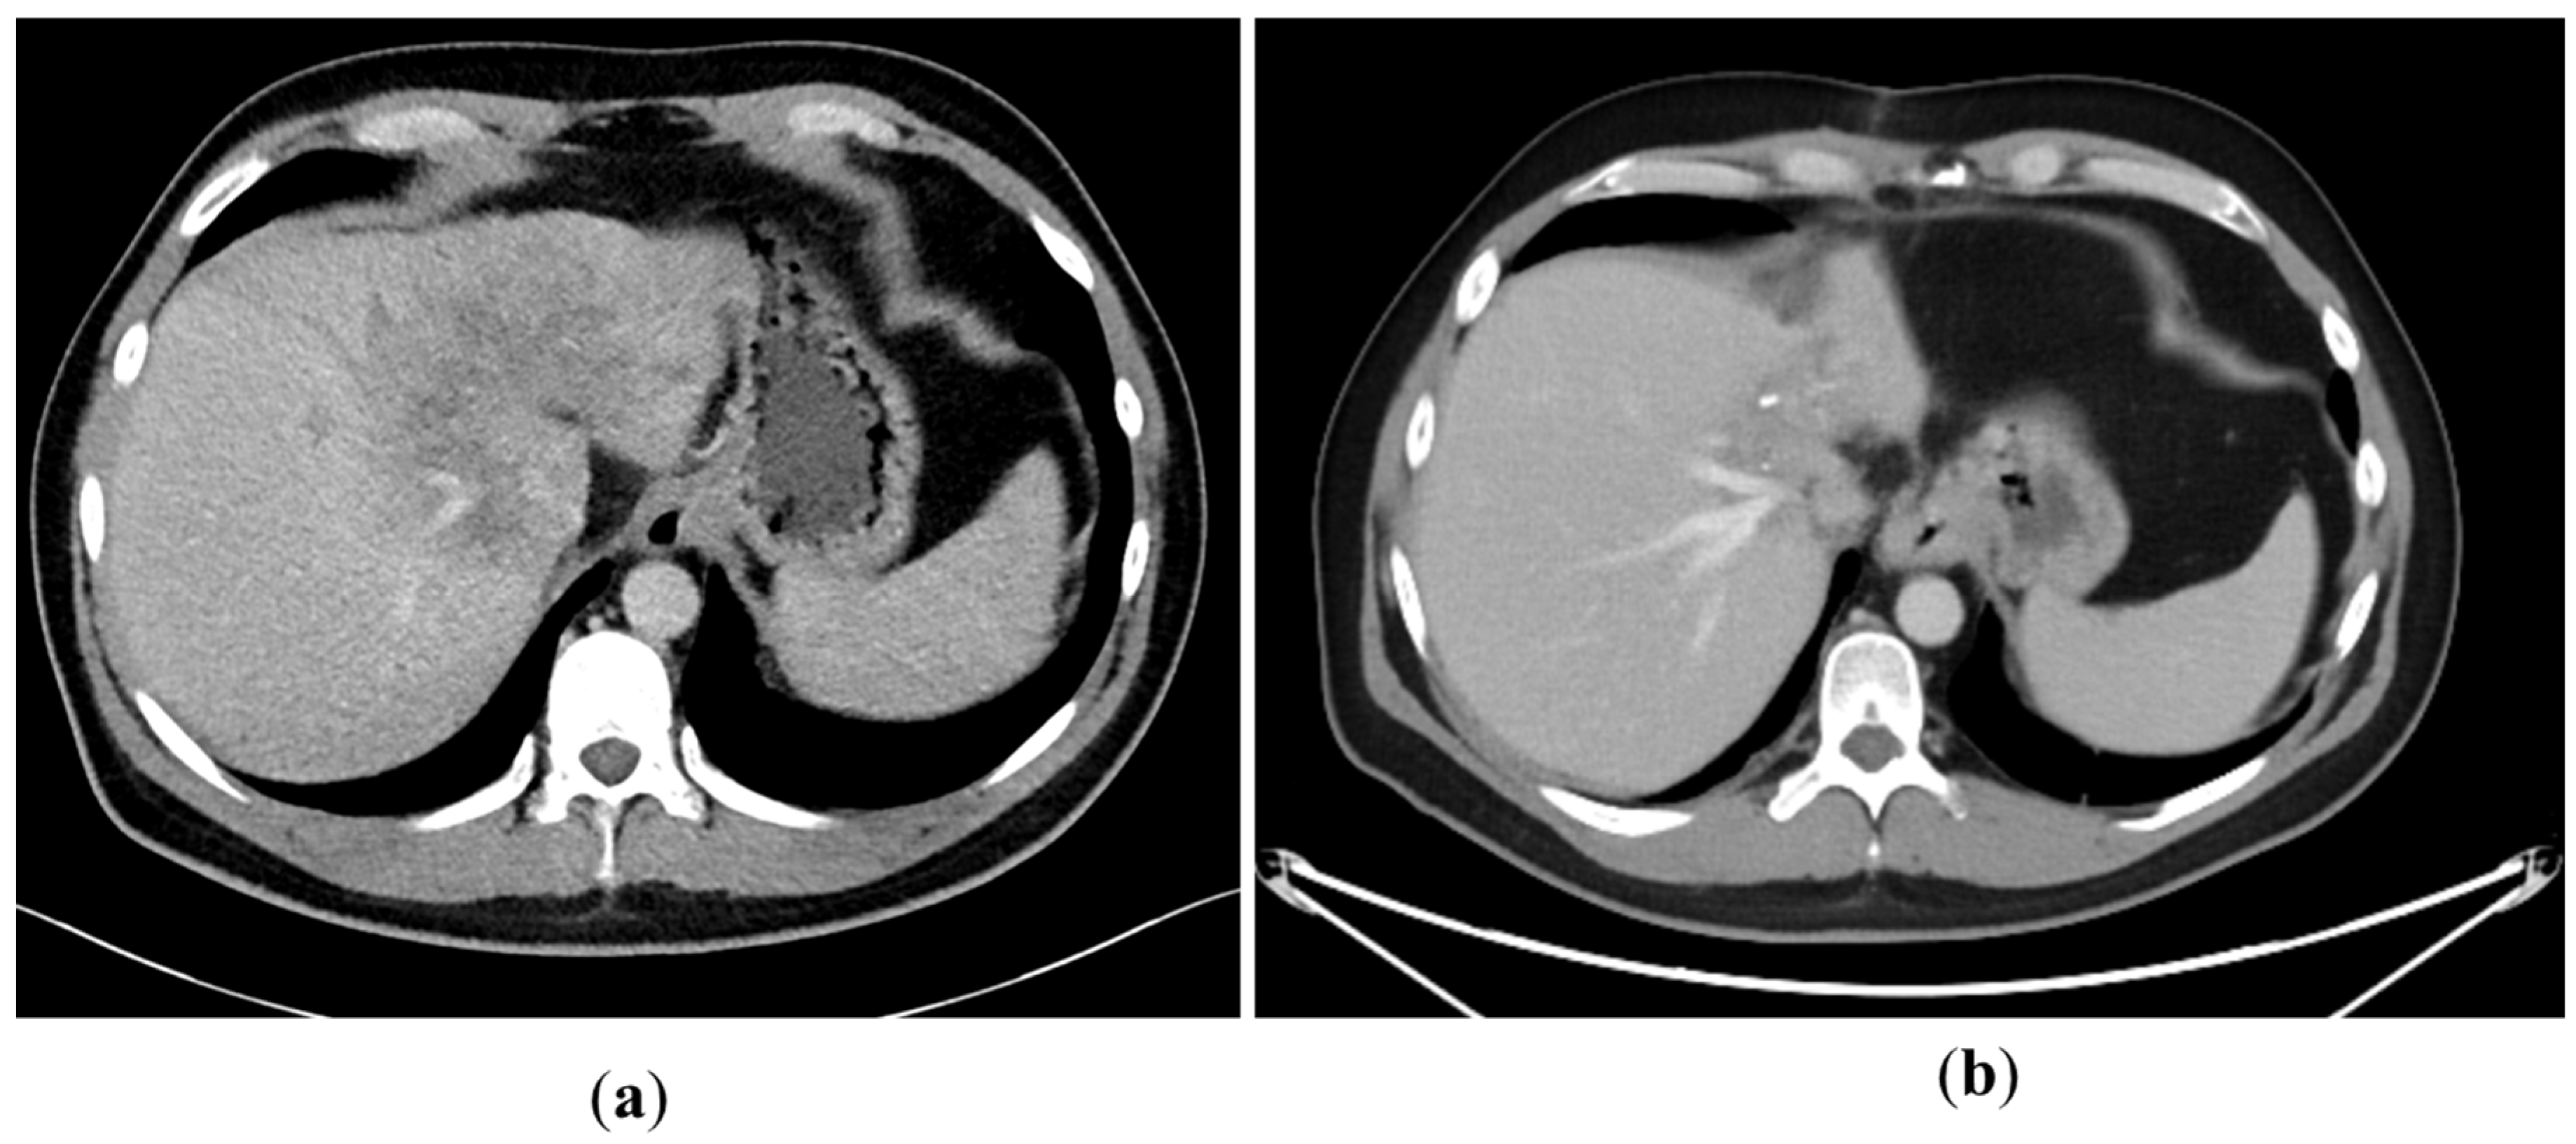

A 43-year-old man went because of persistent fatigue to the general practitioner. The diagnostic showed a large tumor within the central liver (see Figure 1a), which was biopsy-proven as a moderate-differentiated intrahepatic cholangiocarcinoma. An extrahepatic tumor spread could be ruled out (applying an FDG-PET-CT scan, see Figure 2a). Due to the invasion of the hepatic veins, which precluded a primary resection, chemotherapy with cisplatin / gemcitabine was initiated. The tumor showed a partial response (see Figure 1b). We decided to perform surgical exploration with the intent of an ex situ liver resection. Due to an invasion in liver segment VII, even an extended left trisegmentectomy was not possible. We performed an SIRT of both liver lobes resulting in a further, even metabolic (Standardized Uptake Value, SUVmean of the tumor in the initial PET scan: 7.3; SUVmean after treatment: 3.0), response of the tumor (see Figure 2a,b). The CA19-9 levels were always below the reference value. Twenty-two months after the initial diagnosis, the patient could be transplanted with a right living donor lobe from a friend. Histopathologic examination showed an intrahepatic cholangiocarcinoma with a maximum diameter of 6.3 cm. The tumor stage was ypT3, N0, L0, V0, Pn0, R0. Currently, 17 months after the LDLT, the patient is recurrence-free and in good clinical health (see Figure 3). The most recent CA19-9 level is 21.3 U/mL (reference value < 27.0 U/mL).

Figure 3. State 15 months after LDLT.